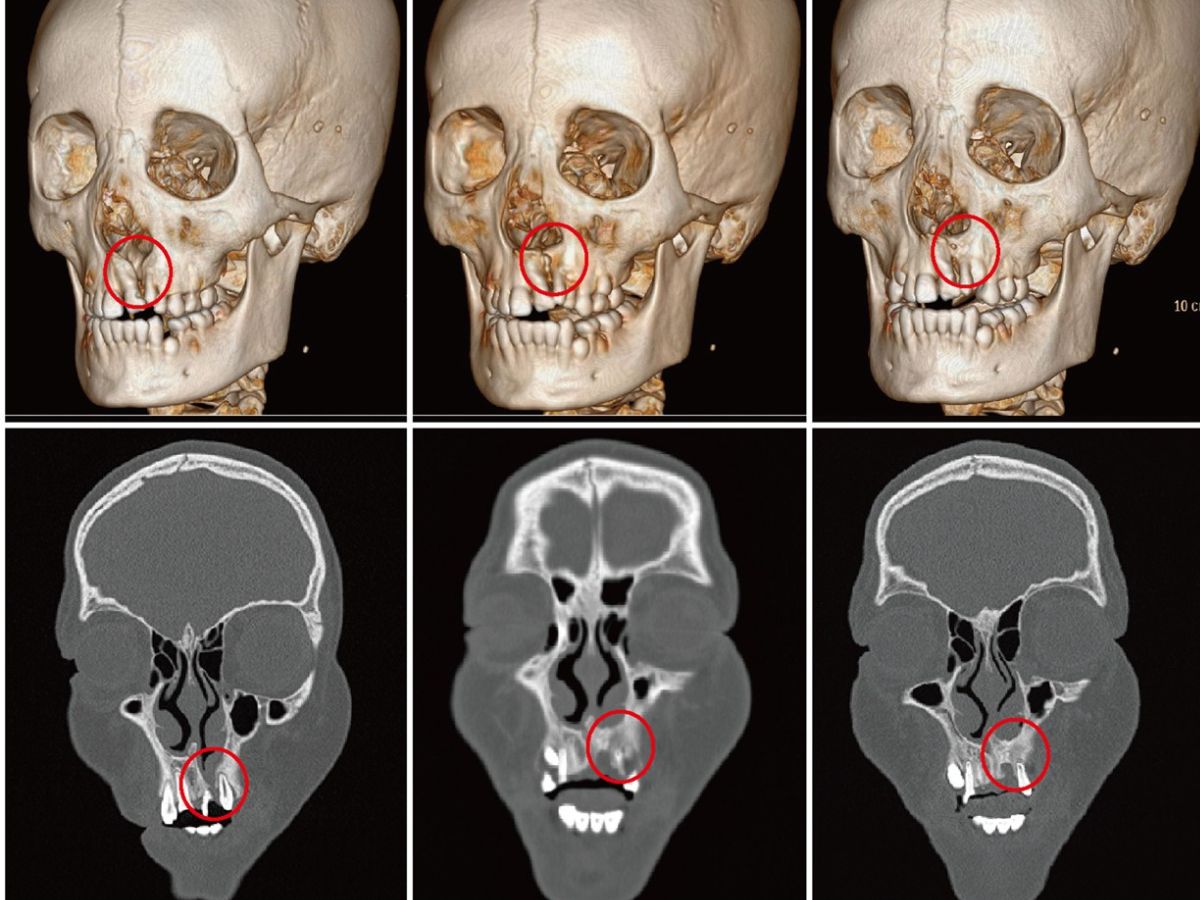

Hình ảnh thực tế kết quả phẫu thuật ghép xương tự thân điều trị khe hở hàm trên

Sau phẫu thuật thành công, trên phim X-quang sau 6 tháng, ta sẽ thấy xuất hiện “cầu xương” liên tục nối liền hai bờ khe hở. Răng nanh sẽ từ từ di chuyển và mọc xuyên qua khối xương mới tái tạo này một cách tự nhiên.